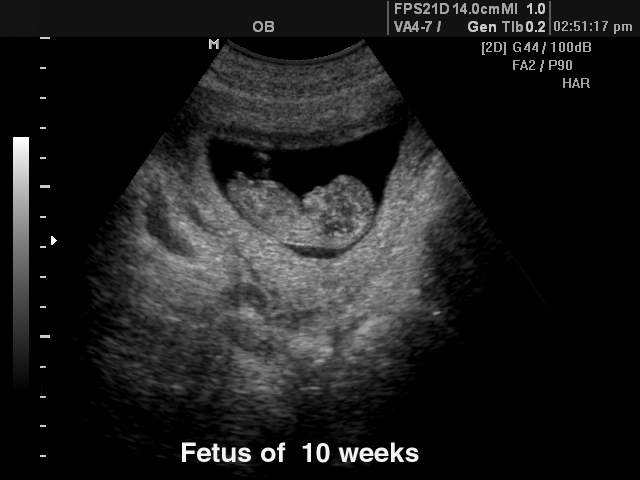

Скриниг при беременности позволит увидеть будущего младенца. Плод на сроке беременности 10 недель уже избавился от «хвоста».

Начинают формироваться наружные половые органы, хотя по УЗИ увидеть, кто там, мальчик или девочка, еще сложно.

Плод уже начинает двигать ручками и ножками, на которых появились крохотные ноготки. Будущий младенец достиг размеров большого абрикоса. Он весит примерно 4-5 г.

У плода появился вкусовой сосочек языка и зачатки зубов. Укрепляется скелет. Кожа покрывается нежным пушком. Современное оборудование дает возможность женщине на сроке 10 недель беременности услышать сердцебиение малыша.

УЗИ на десятой неделе беременности